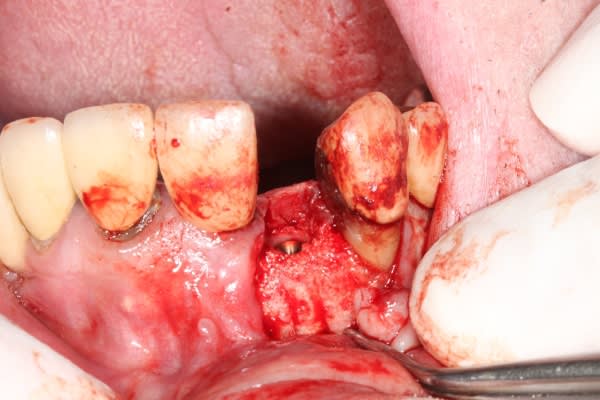

juste pour le plaisir

un petit dernier mis en fonction la semaine dernière

1 pbr75u - Eugenol

2 wlbqqs - Eugenol

3 soqqmc - Eugenol

4 peblmt - Eugenol

5 ebbipt - Eugenol

Img 8465 fqhxid - Eugenol

Juste une remarque sur tes photos Michael, puisque sur la chirugie tu maitrises parfaitement : irrigues ton site avant de prendre une photo et enlèves les taches de sang sur les dents adjacentes, ça ne change en rien la qualité de ton travail, mais c'est plus propre et plus agréable à regarder.